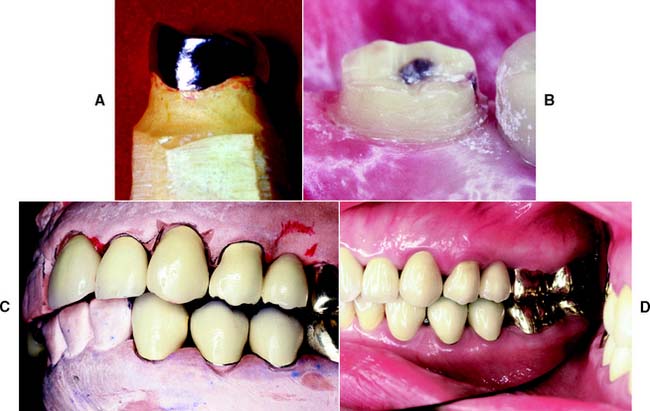

Successful tooth preparation and subsequent restoration depend on simultaneous consideration of all these factors. Improvement in one area often adversely affects another area, and striving for perfection in one may lead to failure in another. For example, in the fabrication of a metal-ceramic crown (see Chapter 24), sufficient thickness of porcelain is necessary for a lifelike appearance. However, if too much tooth structure is removed to accommodate a greater thickness of porcelain for esthetic reasons, the pulpal tissue may be traumatized (biologic consideration) and the tooth unduly weakened (mechanical consideration). In-depth knowledge and an understanding of the various criteria are prerequisite to the development of satisfactory tooth preparation skills. Predictable accomplishment of optimum tooth preparation (Fig. 7-1) often includes finding the best combination of compromises among the applicable biologic, mechanical, and esthetic considerations.

Gingival inflammation is commonly associated with crowns and fixed dental prosthetic abutments that have excessive axial contours, probably because it is more difficult for the patient to maintain plaque control around the gingival margin24 (Fig. 7-15). A tooth preparation must provide sufficient space for the development of good axial contours. This enables the junction between the restoration and the tooth to be smooth and free of any ledges or abrupt changes in direction.

Fig. 7-15 A, Unhealthy gingival tissue resulting from overcontoured restorations. B, The tooth preparations are underreduced; C, Once the restorations are recontoured, gingival health returns.

Under most circumstances, a crown should duplicate the contours and profile of the original tooth (unless the restoration is needed to correct a malformed or malpositioned tooth). If an error is made, a slightly undercontoured flat restoration is better because it is easier to keep free of plaque; however, increasing proximal contour on anterior crowns to maintain the interproximal papilla25 (see Chapter 5) may be beneficial. Sufficient tooth structure must be removed to allow the development of correctly formed axial contours (Fig. 7-16), particularly in the interproximal and furcation areas of posterior teeth, where periodontal disease often progresses with serious consequences.